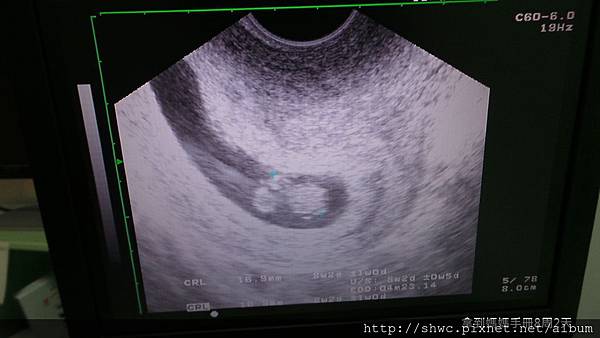

醫師作了子宮抹片,還有陰道超音波檢查,從超音波來看小樹大約1.69公分,週數估計8周又兩天,預產期是明年四月23日。

不過能夠聽到小樹的小小心跳聲,還有看見他小小的樣子,就會希望他可以健康的來到我們身邊。